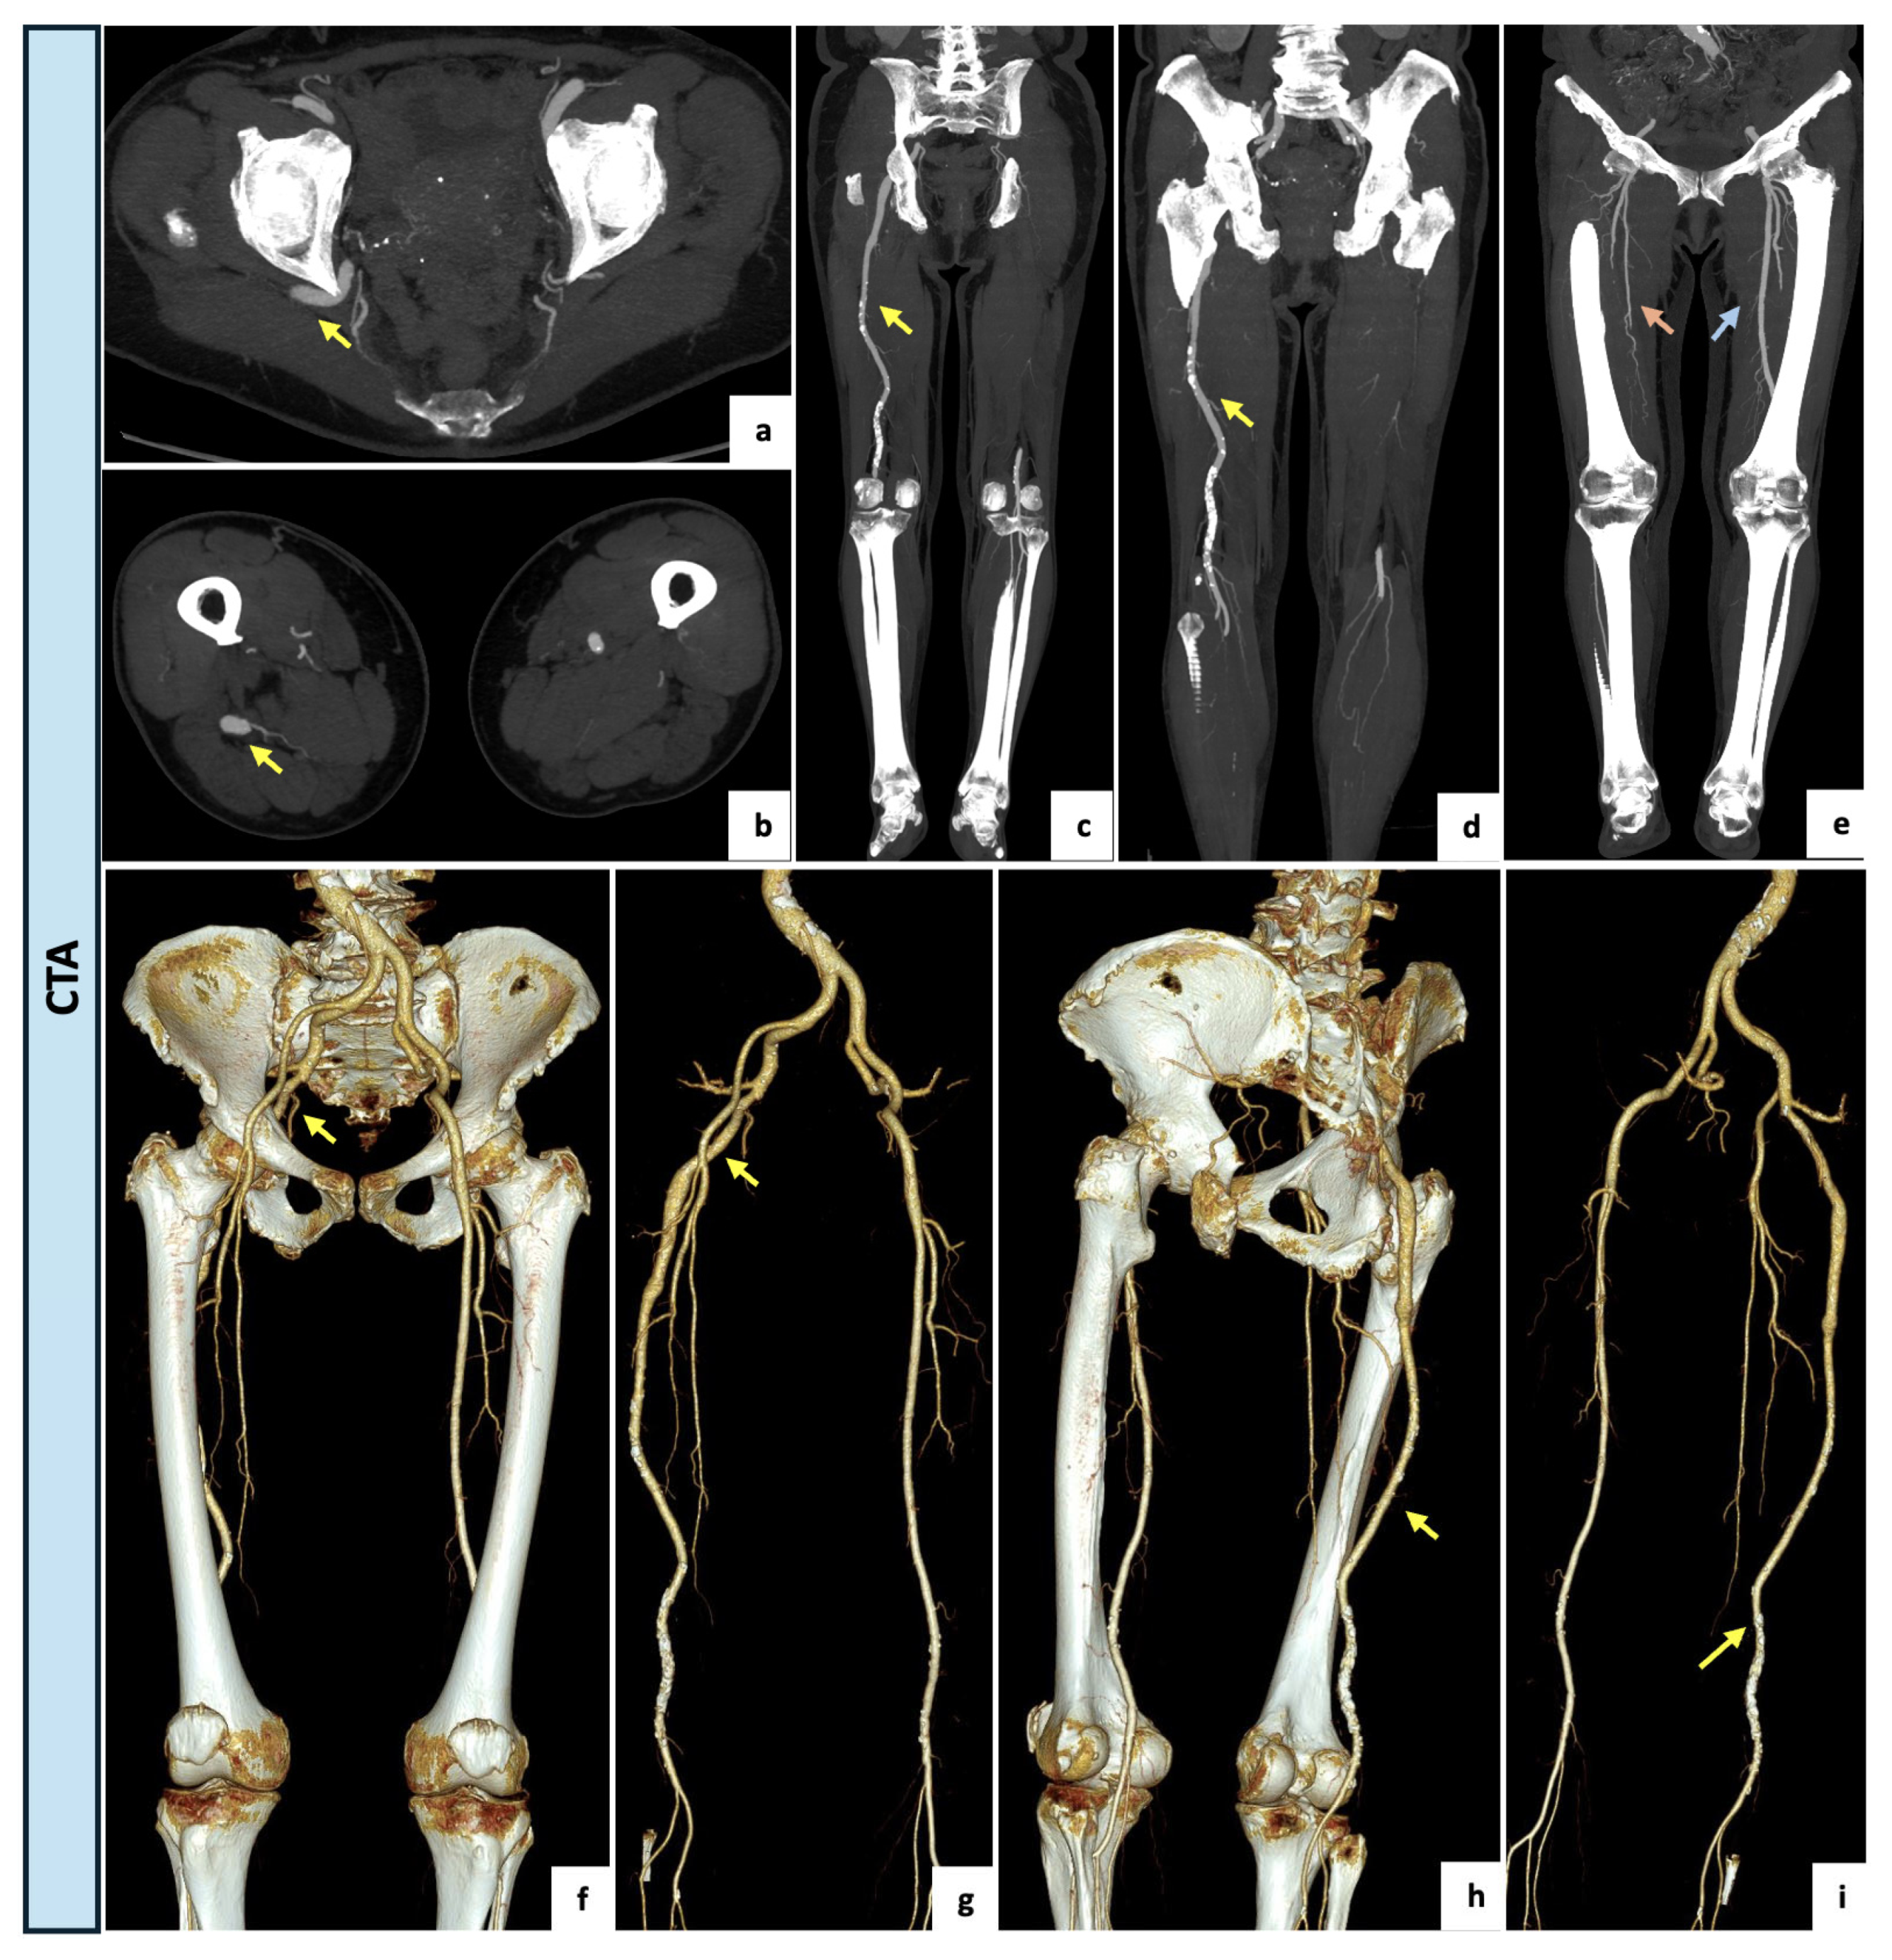

Figure 4.

(a–d) Axial and coronal maximal intensity projection views of the CTA demonstrating a right complete and ectatic PSA of 13 mm (yellow arrow) originating from the internal iliac artery and accompanied by an incomplete ipsilateral SFA interrupted at Hunter’s canal (type 2a). (e) Coronal view of lower limbs with a right incomplete ipsilateral SFA (orange arrow) and a regular contralateral femoral axis (blue arrow) (f–i) Three-dimensional reconstructions showing the ectatic PSA (yellow arrow) running through the greater sciatic notch, following the proximal course of the sciatic nerve and continuing as popliteal–tibial axis.